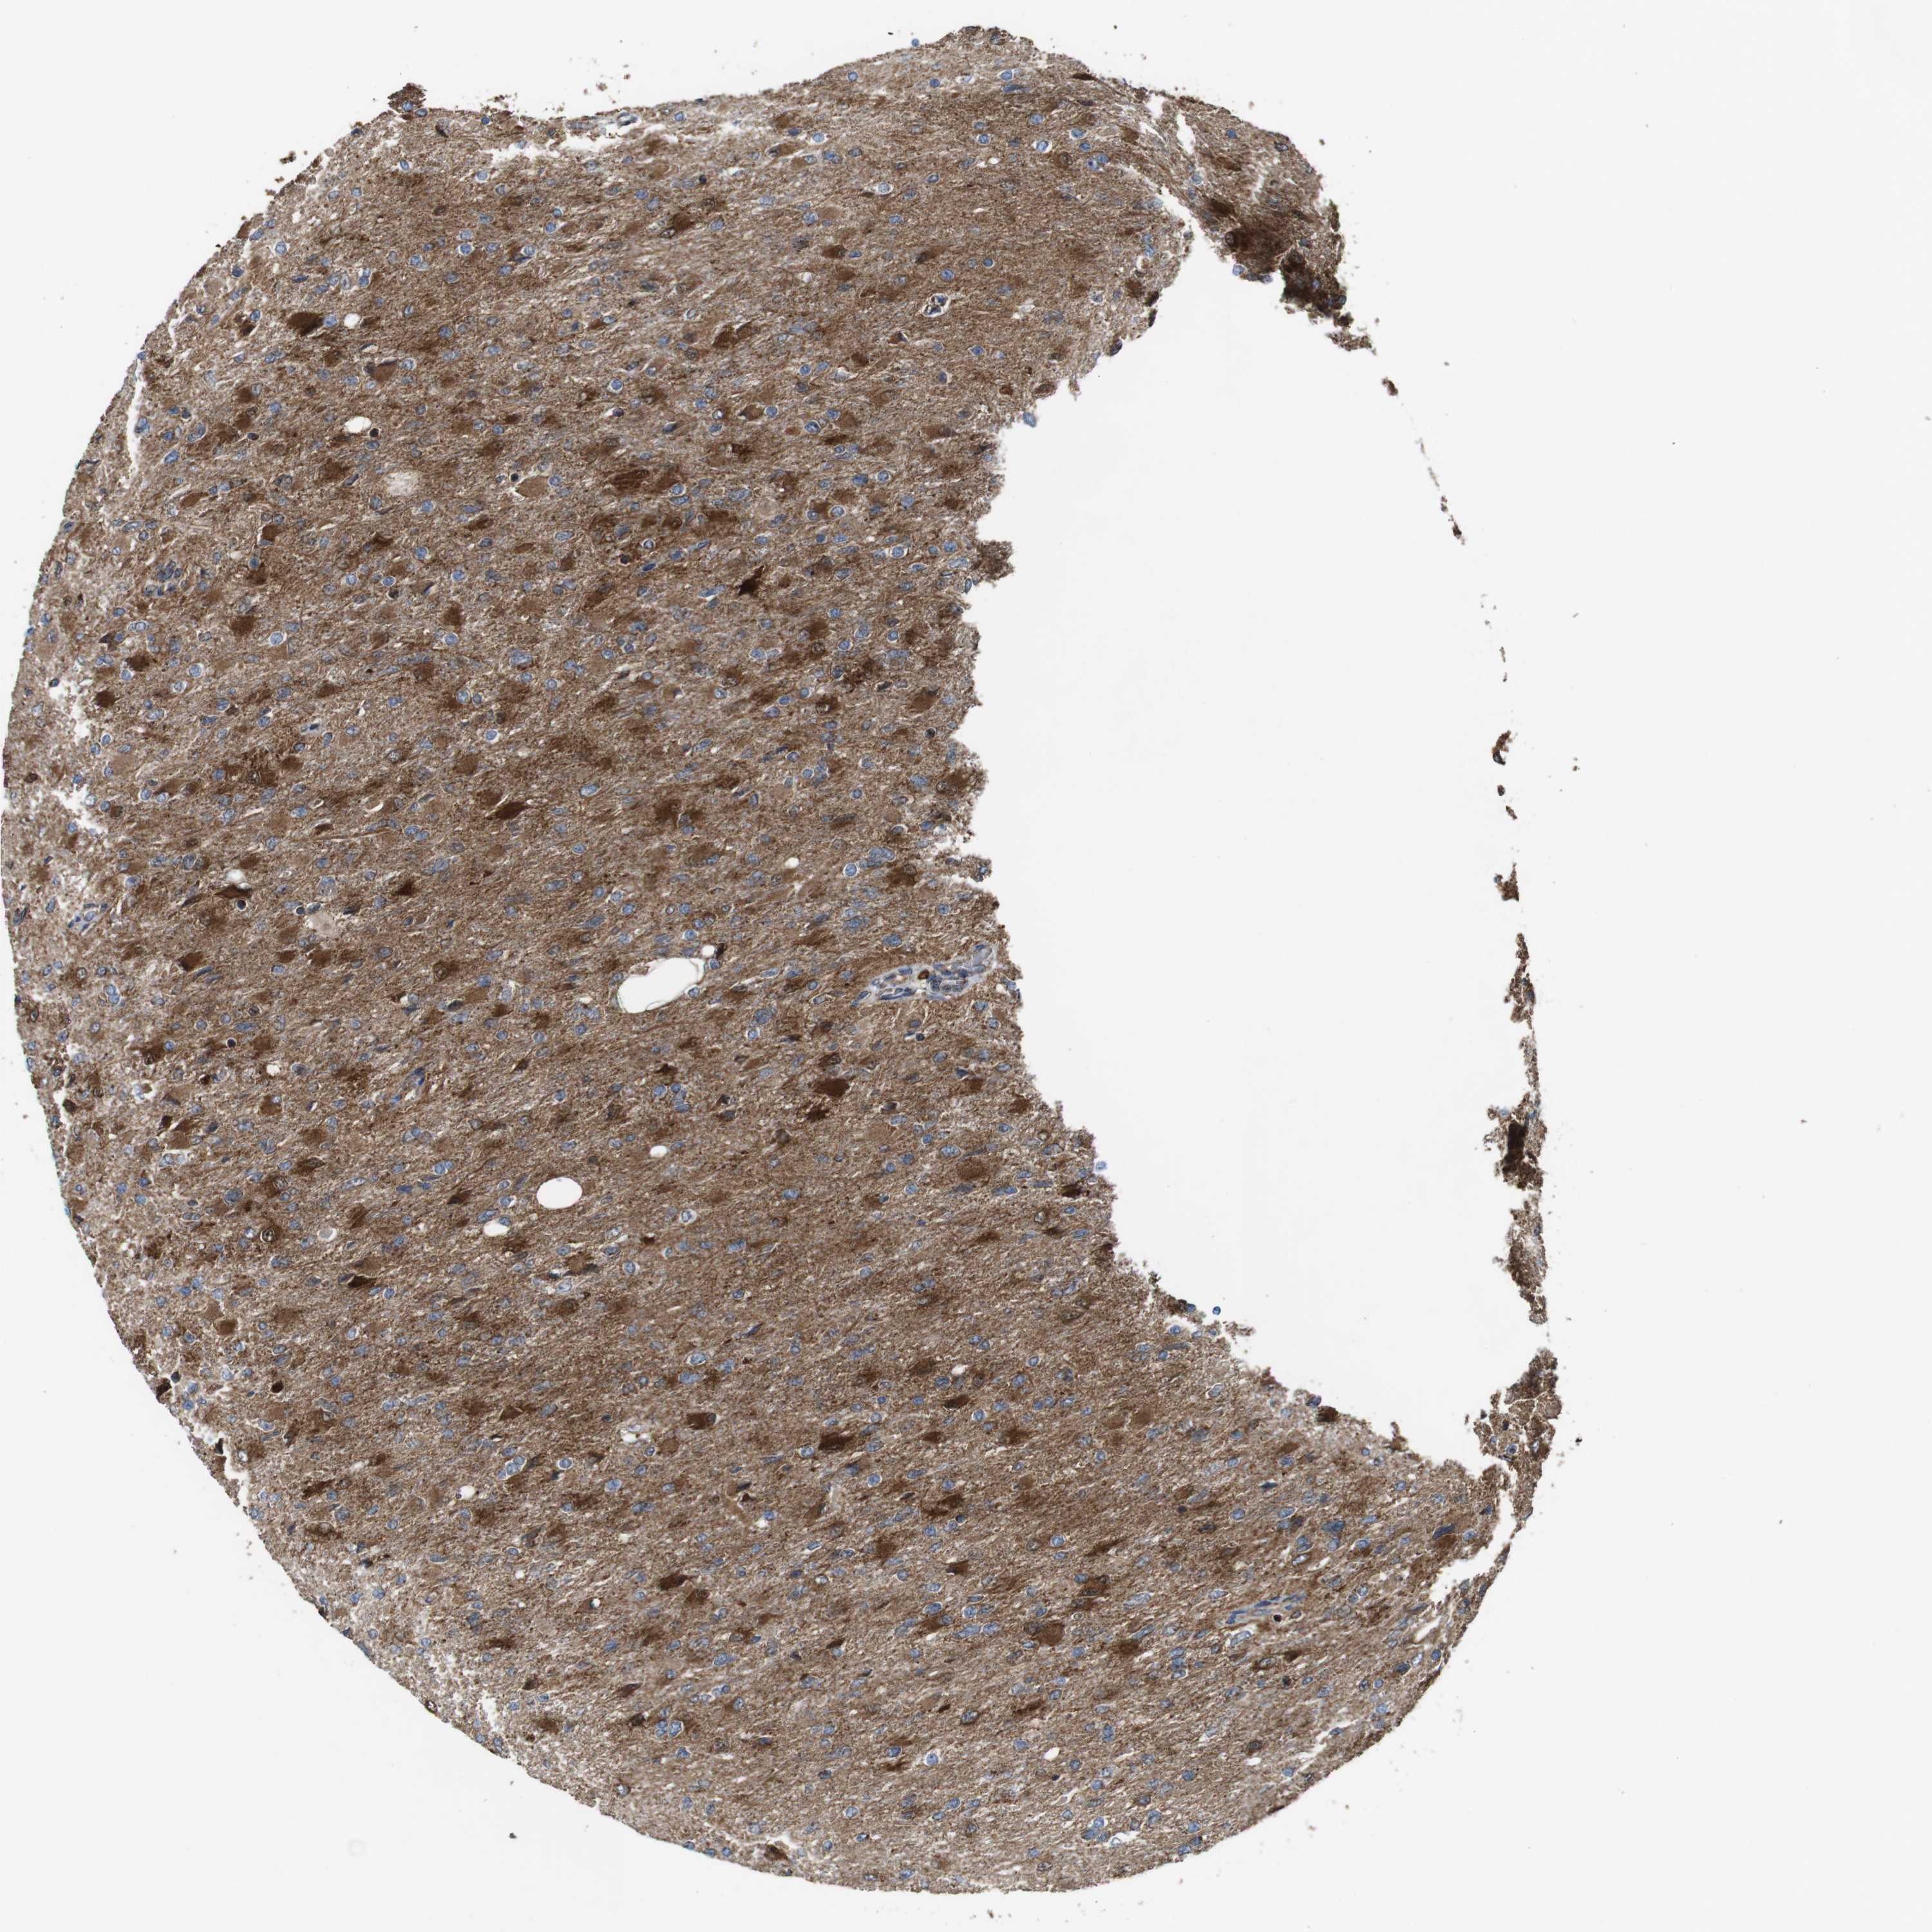

GLIOMA - Protein expressioni

A mouse-over function shows sample information and annotation data. Click on an image to view it in a full screen mode. Samples can be filtered based on level of antibody staining by selecting one or several of the following categories: high, medium, low and not detected. The assay and annotation is described here.

Note that samples used for immunohistochemistry by the Human Protein Atlas do not correspond to samples in the TCGA dataset.

Antibody stainingi

Antibody staining in the annotated cell types in the current human tissue is reported as not detected, low, medium, or high, based on conventional immunohistochemistry profiling in selected tissues. This score is based on the combination of the staining intensity and fraction of stained cells.

Each image is clickable and will lead to virtual microscopy that enables deeper exploration of all samples and also displays staining intensity scores, fraction scores and subcellular localization as well as patient and tissue information for each sample.

Antibody HPA007043

Antibody HPA007044

Antibody CAB010052

Staining

High

Medium

Low

Not detected

Intensity

Strong

Moderate

Weak

Negative

Quantity

>75%

75%-25%

<25%

None

Location

Nuclear

Cytoplasmic/membranous

Cytoplasmic/membranous,nuclear

Glioma, malignant, High grade

Glioma, malignant, Low grade